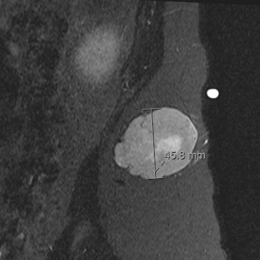

• • The work-up often consists of a physical examination, X-rays, CT scans, MRI, and sometimes bone scans are required.

• • MRI is the best imaging because it is the most sensitive.

Radiographic imaging is used to help form a diagnosis. These include X-Ray, MRI, CT and Bone Scans

An example of a MRI is shown.